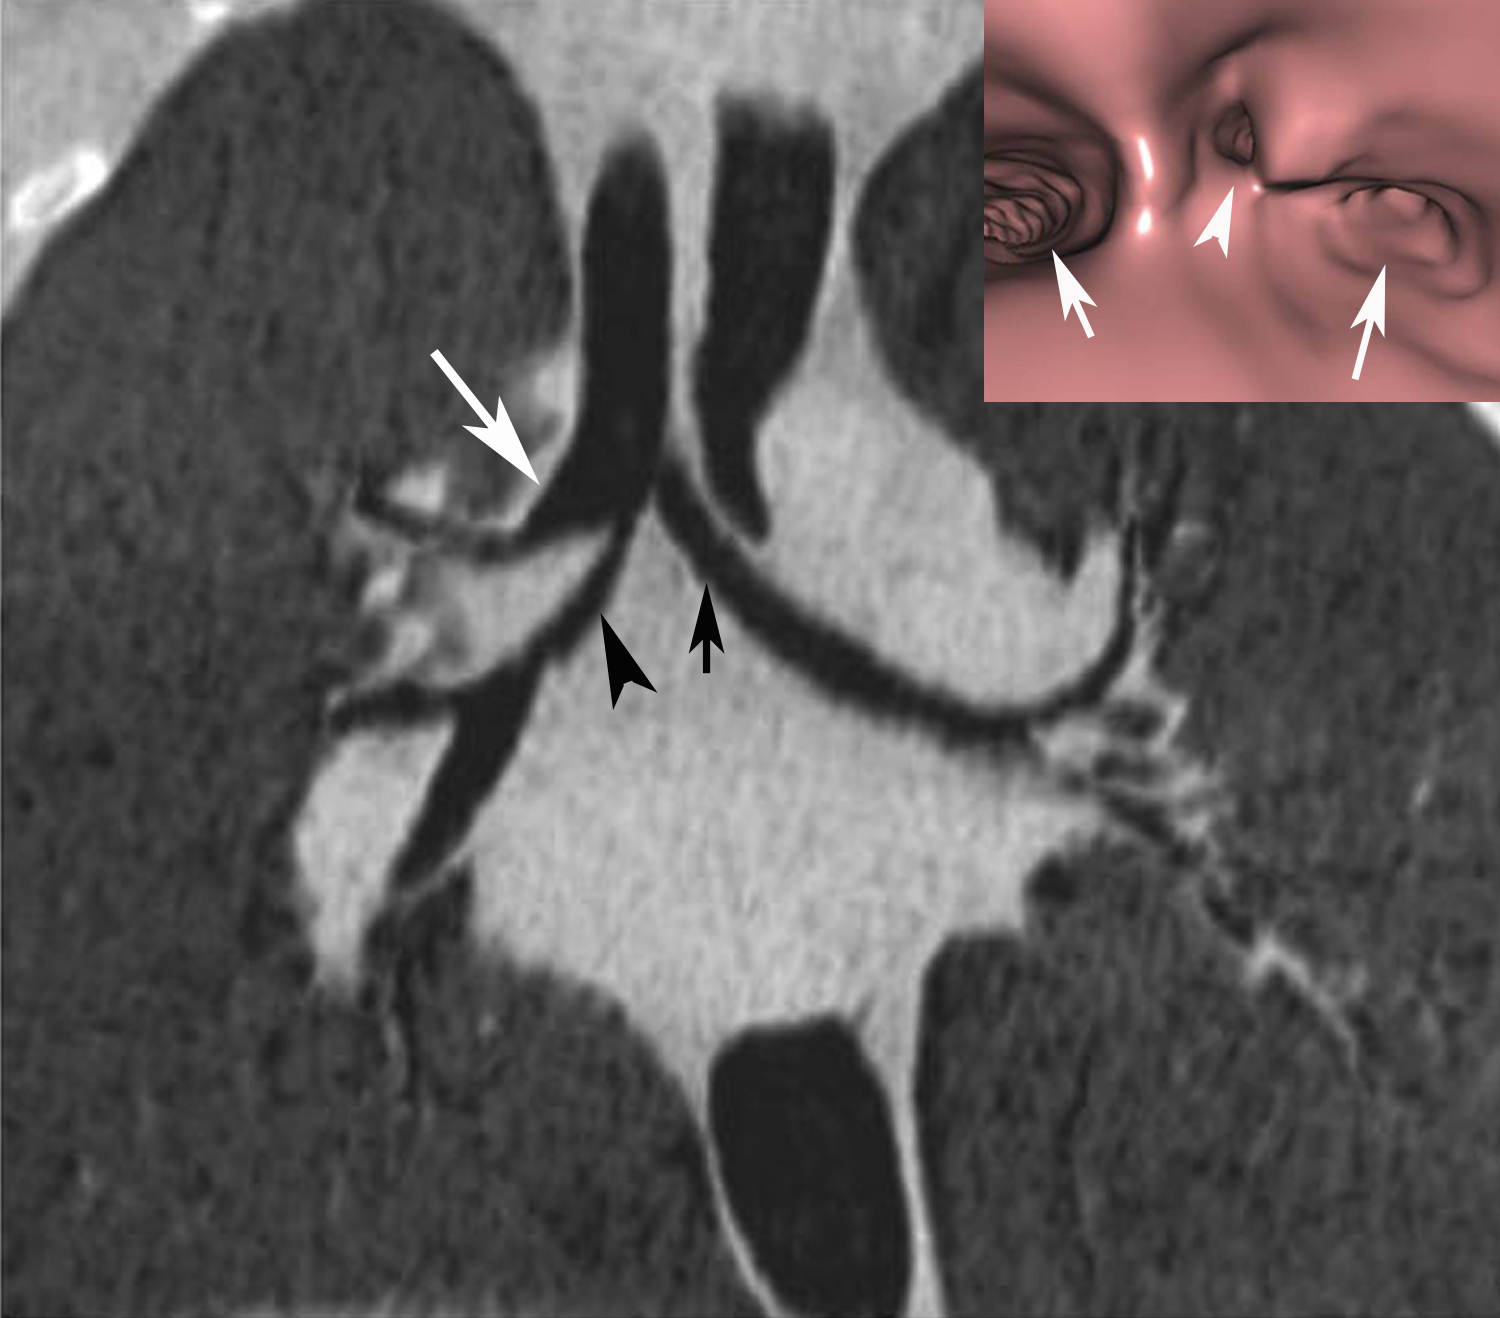

From www.cureus.com

Cureus Intraoperative Diagnosis of "Bronchus Suis", a Variant of Tracheal Bronchial Bronchiectasis Bronchiectasis damages your airways, making it hard to clear mucus. bronchiectasis is an irreversible widening (dilation) of portions of the breathing tubes or airways (bronchi) resulting from damage to the airway. bronchiectasis is a chronic lung disease characterized by persistent and lifelong widening of the bronchial airways and weakening of. more common than central airway disease is. Tracheal Bronchial Bronchiectasis.

From radiologykey.com

Airways Radiology Key Tracheal Bronchial Bronchiectasis tracheal/bronchial involvement may cause: more common than central airway disease is peripheral bronchial wall thickening and bronchiectasis, as well as. Bronchiectasis damages your airways, making it hard to clear mucus. bronchiectasis is a chronic lung disease characterized by persistent and lifelong widening of the bronchial airways and weakening of. a bronchial aspiration or bronchial wash targeting. Tracheal Bronchial Bronchiectasis.